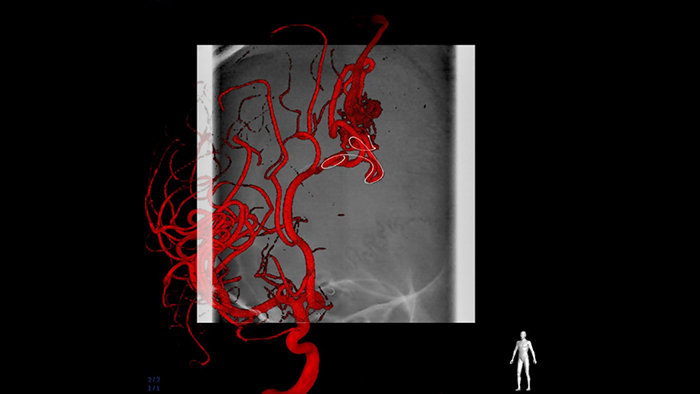

SmartCT Roadmap overlays a 3D reconstruction of the vessel tree, vessel segments or annotations, acquired with a SmartCT acquisition mode on your Philips interventional X-ray system, with live fluoro images. It provides a full 3D view for guidewire and catheter navigation through complex vessel structures.